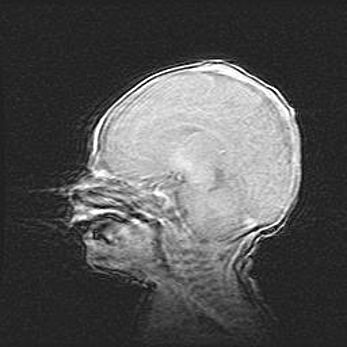

Открытая гидроцефалия.

Возраст: 9 месяцев 12 дней

Вес: 6800 г

Пол: мужской

Окружность головы: 41,5 см

Срок гестации: 28 недель

Гидроцефалия головного мозга у новорожденных имеет характерный признак: опережающий рост окружности головы приводит к визуально хорошо определяемой гидроцефальной форме сильно увеличенного в объёме черепа. Детские неврологи определяют следующие симптомы гидроцефалии у грудничков: выбухающий напряжённый родничок, частое запрокидывание головы, смещение глазных яблок к низу.